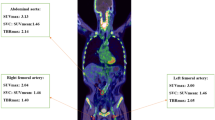

Imaging protocols for 18FDG-PET-CT have been described in detail in previous publications [12]. 18FDG-PET-CT scans were performed using a Siemens Biograph mCT scanner. Subjects fasted for at least 6 h prior to infusion of 200 MBq of 18F-FDG (5.5 mCi). Before PET scanning, a low-dose CT was performed for the attenuation of correction, anatomic coregistration, and fusion of PET-CT images (multiple times). The maximum standard uptake values (SUV) of 18F-FDG were measured in an axial orientation along each carotid artery from 1 cm up to 3 cm below the bifurcation, which was performed by manually drawing the circular regions of interest that encompassed the vessel wall. The target-to-background ratio (TBR) was calculated from the ratio of the maximal arterial standardized uptake values and mean venous background activity within the superior vena cava (correction for aorta) and the jugular vein (correction for carotids). After the 18F-FDG infusion, the PET images of the subjects were collected every 10 min until the 18F-FDG uptake levels entered the plateau stage [13] (Fig. 1).

Characteristics of 18F-FDG uptake in atherosclerotic plaques

Significant 18F-FDG uptake was shown in atherosclerotic plaques, as evidenced by the local concentration of 18F-FDG in the vascular wall of the diseased segments. These plaques showed different 18F-FDG uptake levels, with the highest uptake levels reaching 3.0, while the lowest levels reached only 1.4. In addition, significant differences in the 18F-FDG uptake velocity were also found, with 24 subjects reaching peak values in only 15 min (group A), 32 subjects in 25 min (group B), 28 subjects in 35 min (group C), 48 subjects in 45 min (group D), and, in the slowest group, 24 subjects in 55 min (group E). Furthermore, there was no correlation between the 18F-FDG uptake levels and 18F-FDG uptake velocity in any subjects (r = 0.103, p = 0.637).